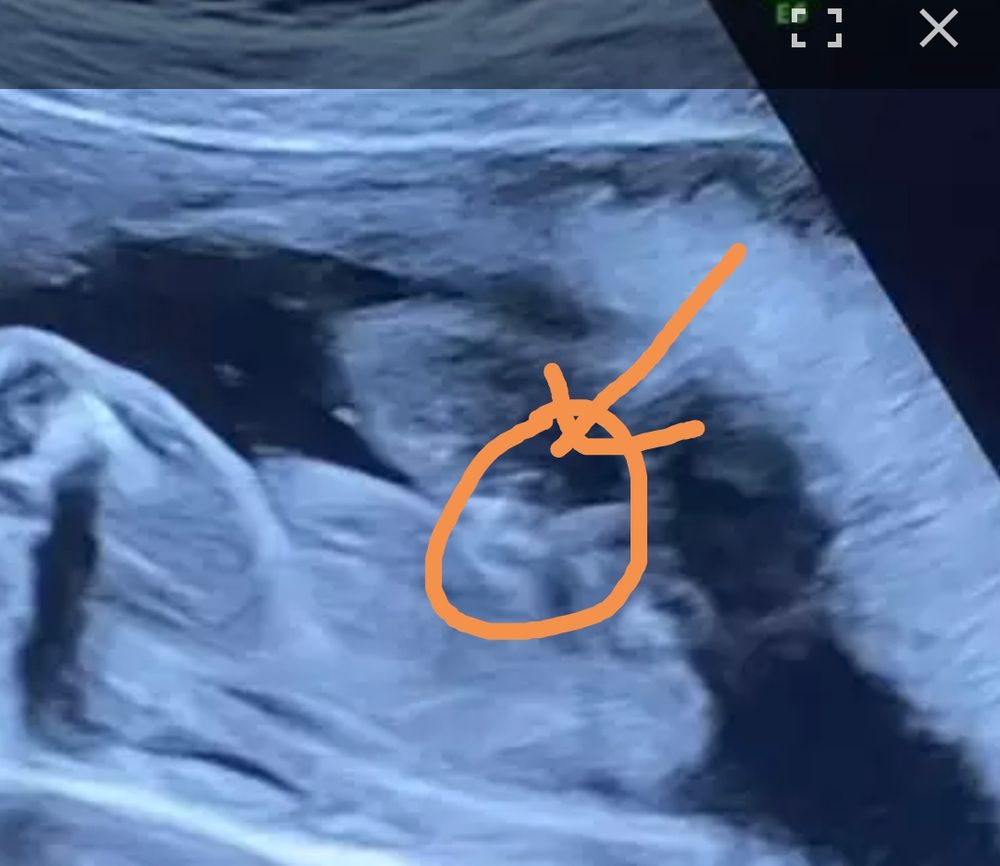

Девочки, кто какой пол малыша видит на фото?) фото снизу, справа попка, чуть левее пяточка

Не знаю, мне видится мальчик... Но фото на таком сроке должно быть снизу попы.

это фото со 2-го скрининга! Скоро 3-й, на узи не говорили, это я сама с видео скрины делала 😂

ножки зажаты, поэтому сама не понимаю🙃

Стрелка наведена на писюнсик , я вижу так ,